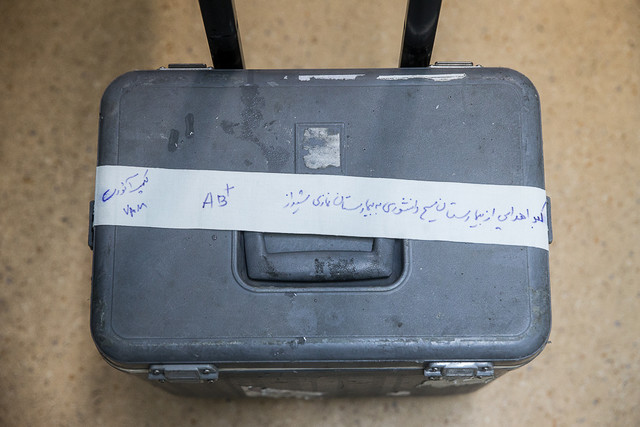

انجام اولین پیوند کبد از دهنده زنده در بیمارستان فیروزگر رئیس تیم پیوند کبد مرکز آموزشی درمانی فیروزگر از انجام موفقیت آمیز اولین عمل پیوند کبد از دهنده زنده در این بیمارستان خبر داد. به گزارش مشهدنیوز/ دکتر محسن رضا منصوریان با بیان اینکه اولین پیوند کبد از دهنده زنده در تاریخ ۲۳ آبان ۱۳۹۹ با […]